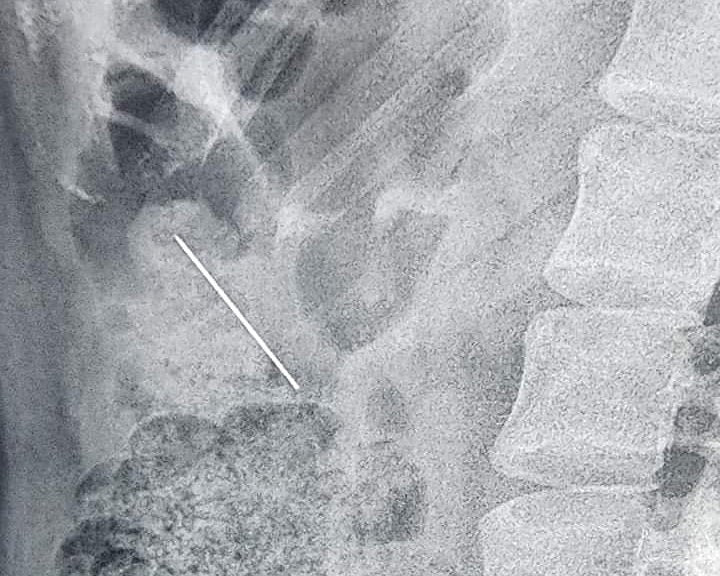

এই চিকিৎসক বলেন, সুমাইয়াকে সন্ধ্যায় শহরের একটি বেসরকারি ক্লিনিকে নিয়ে এলে তিনি এক্স–রে করে পিনটির অবস্থান দেখেন। পরে অস্ত্রোপচার ছাড়াই আধা ঘণ্টার চেষ্টায় অ্যান্ডোসকপি করে ফরেন বডি ফরসেপ দিয়ে পিনটি বের করে আনেন। পিনটি নাভির কাছাকাছি গিয়ে গেঁথে ছিল। তিনি কখনো মুখে পিন না নেওয়ার পরামর্শ দেন।